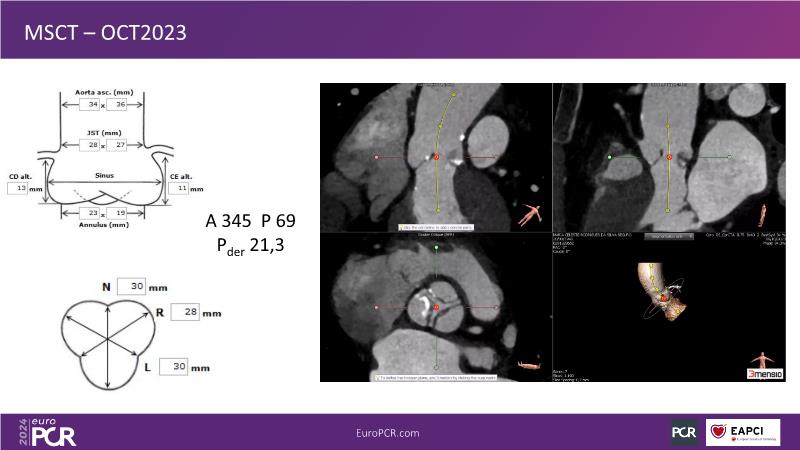

Watch this session to learn the best practices for treating aortic stenosis, with a focus on lifetime management. Gain insights into evaluating patient anatomy and clinical presentation to anticipate the need for a second valve, understand different valve designs and their initial selection, and observe a straightforward ACURATE valve implantation. Additionally, explore considerations for TAV-in-TAV procedures, the importance of CT planning, and future steps for treating younger patients.

- To experience the additional value of simulations when planning for coronary access after TAVI and redo TAVI